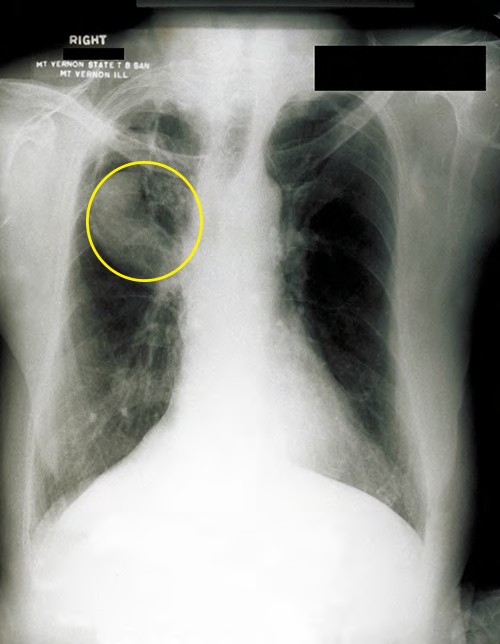

After inhalation, the bacteria enter the alveoli (Figure 22.13). The cells are phagocytized by macrophages but can survive and multiply within these phagocytes because of the protection by the waxy mycolic acid in their cell walls. If not eliminated by macrophages, the infection can progress, causing an inflammatory response and an accumulation of neutrophils and macrophages in the area. Several weeks or months may pass before an immunological response is mounted by T cells and B cells. Eventually, the lesions in the alveoli become walled off, forming small round lesions called tubercles. Bacteria continue to be released into the center of the tubercles and the chronic immune response results in tissue damage and induction of apoptosis (programmed host-cell death) in a process called liquefaction. This creates a caseous center, or air pocket, where the aerobic M. tuberculosis can grow and multiply. Tubercles may eventually rupture and bacterial cells can invade pulmonary capillaries; from there, bacteria can spread through the bloodstream to other organs, a condition known as miliary tuberculosis. The rupture of tubercles also facilitates transmission of the bacteria to other individuals via droplet aerosols that exit the body in coughs. Because these droplets can be very small and stay aloft for a long time, special precautions are necessary when caring for patients with TB, such as the use of face masks and negative-pressure ventilation and filtering systems.

Eventually, most lesions heal to form calcified Ghon complexes. These structures are visible on chest radiographs and are a useful diagnostic feature. But even after the disease has apparently ended, viable bacteria remain sequestered in these locations. Release of these organisms at a later time can produce reactivation tuberculosis (or secondary TB). This is mainly observed in people with alcoholism, the elderly, or in otherwise immunocompromised individuals (Figure 22.13).